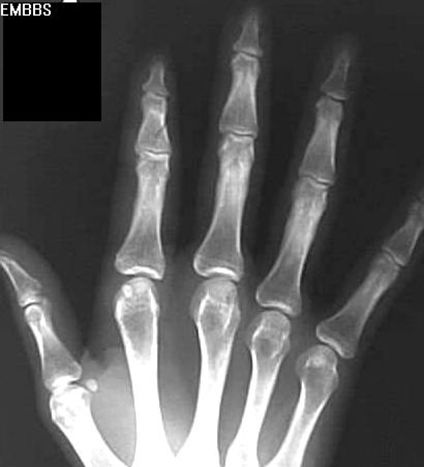

拳击手骨折

握拳撞击

通常发生在第五掌骨

Bennett Fracture

第一掌骨基底部

关节内骨折伴脱位–背侧半脱位

轴向压力

指骨骨折